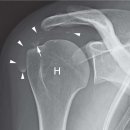

💪 어깨 통증의 진짜 원인 ⚡ 회전근개 파열, 왜 생기고 어떻게 치료할까? 안녕하세요 🙂근육전문 경근학회 입니다. 많은 분들이 어깨 통증을 단순 근육통이나 오십견으로 생각하시지만, 실제로는 **회전근개 파열(rotator cuff tear)**이 원인인 경우가...

chronic cases that fail to improve with other less invasive approaches. (www.actabiomedica.it) 초록 회전근개 석회화 건병증(RCCT)은 회전근개(RC) 또는 견봉하-삼각근하(SASD) 점액낭에 석회화 침착물이 존재하거나 건 주위로 석회화가 확산될 때...

어깨 통증의 원인, 회전근개파열 제대로 알아보기 어깨는 인체에서 움직임이 가장 많은 관절 중 하나로, 운동 범위가 넓은 만큼 손상도 자주 발생합니다. 특히 반복적인 사용이나 외상으로 인해 회전근개파열이 발생하면 팔을 들거나 돌릴 때 극심한 통증...